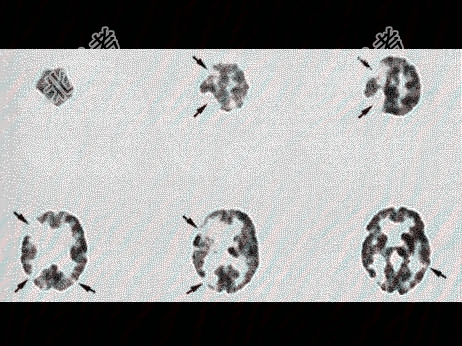

- 单项选择题男,70岁, 反应迟钝,有高血压病史16年, 行99Tcm-HMPAO脑血流灌注显像如图,诊断为( )

A、多发脑梗死

B、PD改变

C、脑转移癌

D、血管性痴呆

E、早老性痴呆